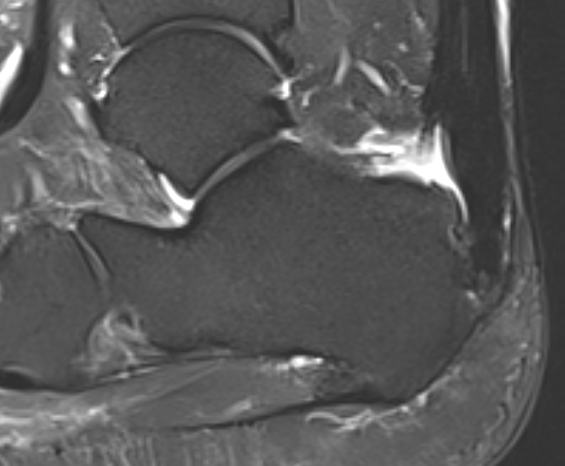

MRI

Retrocalcaneal bursitis with Haglund's

Partial tearing at insertion with retrocalcaneal bursa

Tendon thickening, Haglund's deformity and retrocalcaneal bursa

MRI grading

- Grade I: 6 - 8 mm thickening

- Grade II: > 8 mm tendon thickness with < 50% tendon degeneration

- Grade III: > 8 mm tendon thickness with > 50% tendon degeneration